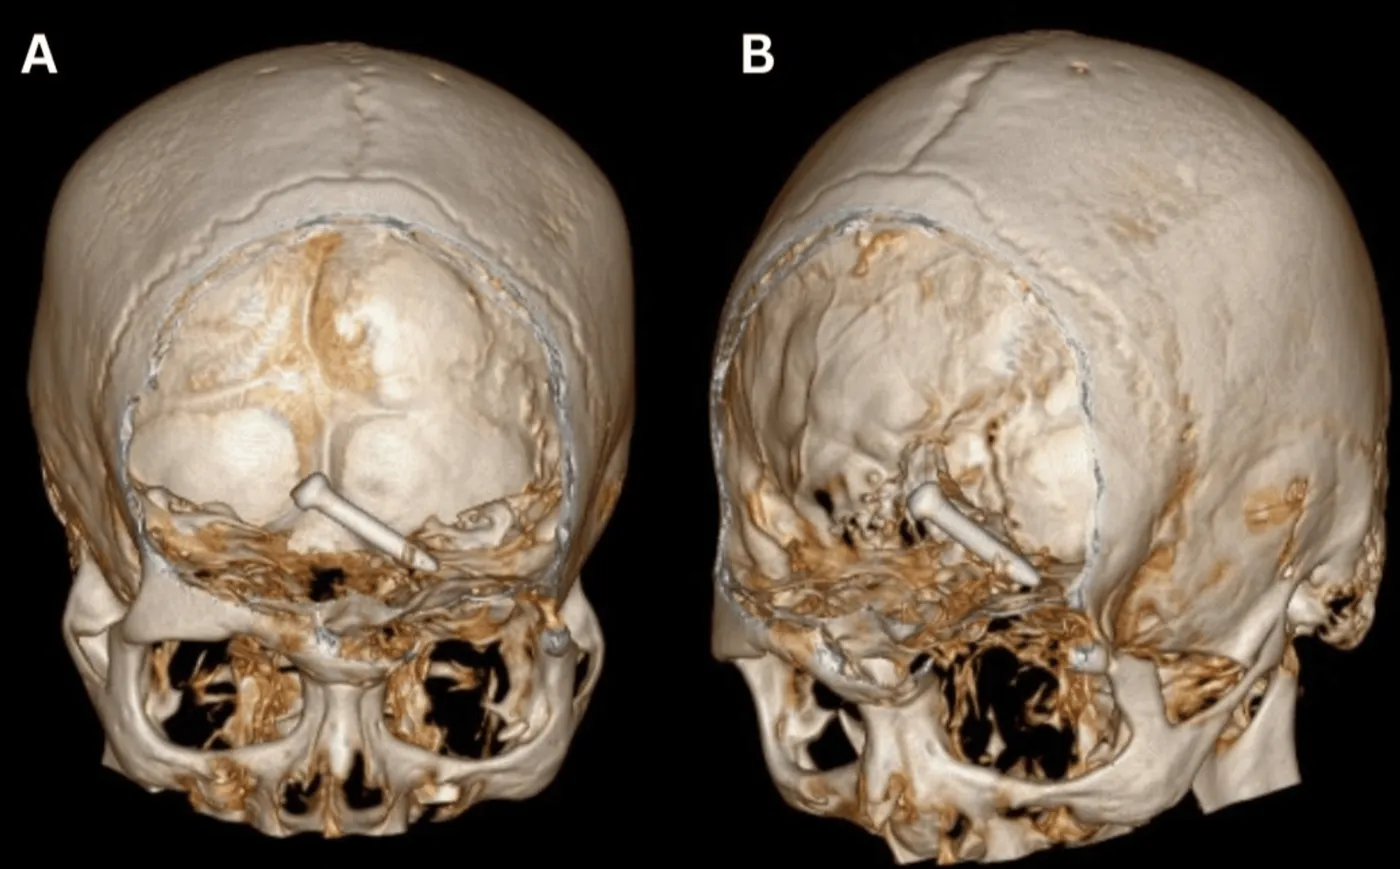

Mężczyzna miał również poważną ranę oka i popękaną kość sklepienia oczodołu. Szczęśliwie, jak pokazały zdjęcia rentgenowskie i tomografia komputerowa czaszki, gwóźdź o milimetry minął gałkę oczną i nie naruszył ważnych naczyń krwionośnych ani kluczowych nerwów, ale z uwagi na poważne uszkodzenie mózgu lekarze nie byli pewni, czy mężczyzna w ogóle przeżyje.

Lekarze ze szpitala Sultanah Bahiyah w mieście Alor Setar, do którego trafił ranny, podali mu potężną dawkę środków przeciwbólowych, antybiotyki, zastrzyk przeciwko tężcowi i leki przeciwpadaczkowe, a następnie przystąpili do operacji.

Zabieg był bardzo skomplikowany, ale chirurgom udało się usunąć gwóźdź w całości, wraz z uszkodzoną tkanką, powstrzymać krwawienie i zszyć ranę. Następnie mężczyzna spędził pięć dni na oddziale intensywnej terapii i jak napisali lekarze, „wrócił do dobrej formy bez deficytów neurologicznych”. Podkreślili jednak, że kiedy wychodził ze szpitala po pięciu dniach, jego lewe oko wciąż nie reagowało na światło, a z powodu opuchlizny po operacji nie mógł prawidłowo zamknąć powieki, jednak nie stwierdzono problemów, które mogłyby wystąpić po tak poważnym uszkodzeniu płata czołowego mózgu.

gwozdz-2-38057533.png

Gwóźdź w mózgu, źródło: „Cureus”